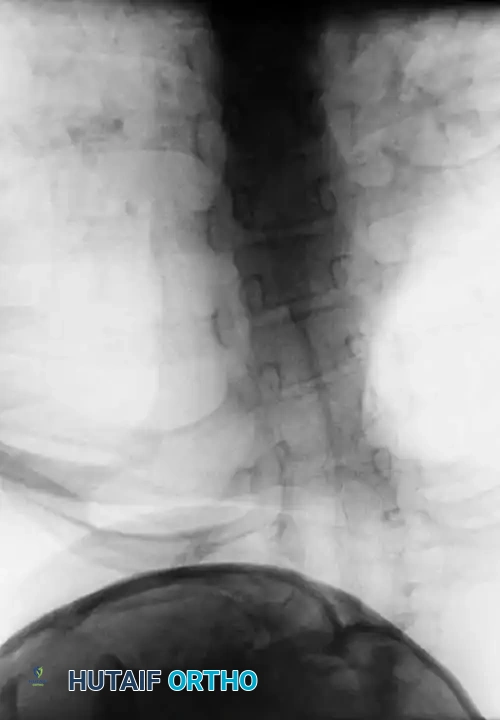

RADIOGRAPHIC EVALUATION

A comprehensive imaging protocol is the cornerstone of KFS management.

Initial evaluation must include high-quality anteroposterior (AP), open-mouth odontoid, and lateral cervical radiographs.

Dynamic Imaging

Lateral flexion-extension views are the most critical plain films obtained. They are essential for identifying occult atlantoaxial instability or hypermobility at an open segment adjacent to a fusion block.